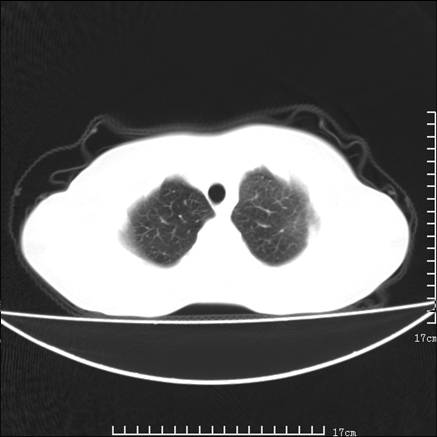

女,46岁,患胃溃疡多年,溃疡大小约1.0cm左右,后于5年前手术,病理为胃癌。主诉:半月前感冒后胸闷,气短,有咳嗽,无明显咳痰,无发热。偶有腰背部不适。

以下为高分辨扫描图像

双肺小叶间增厚,双肺散布粟米影和磨玻璃状影,以双肺上叶为重。结合病史考虑转移(癌性淋巴细管炎)可能性大。

结合病史:认为是典型肺部癌性淋巴管炎、淋巴结转移。请看图解。

正如caihe主任所言,影像表现结合临床病史应该支持肺癌性淋巴管炎;上肺大片边缘不清的渗出病变,多系感染所致,临床有感冒病史并咳嗽表现。肺癌性淋巴管炎临床一般无咳嗽、咳痰症状。

肺癌性淋巴管炎征象分为主要征象及合并征象,主要征象包括:

1、近肺门支气管血管周围间质结节状增厚;

2、小叶间隔结节状增厚;

3、小叶中央间质结节状增厚;

4、胸膜下间质结节状增厚。

合并征象为:纵隔淋巴结增大,胸腔积液,肺多发随机分布的小结节等。